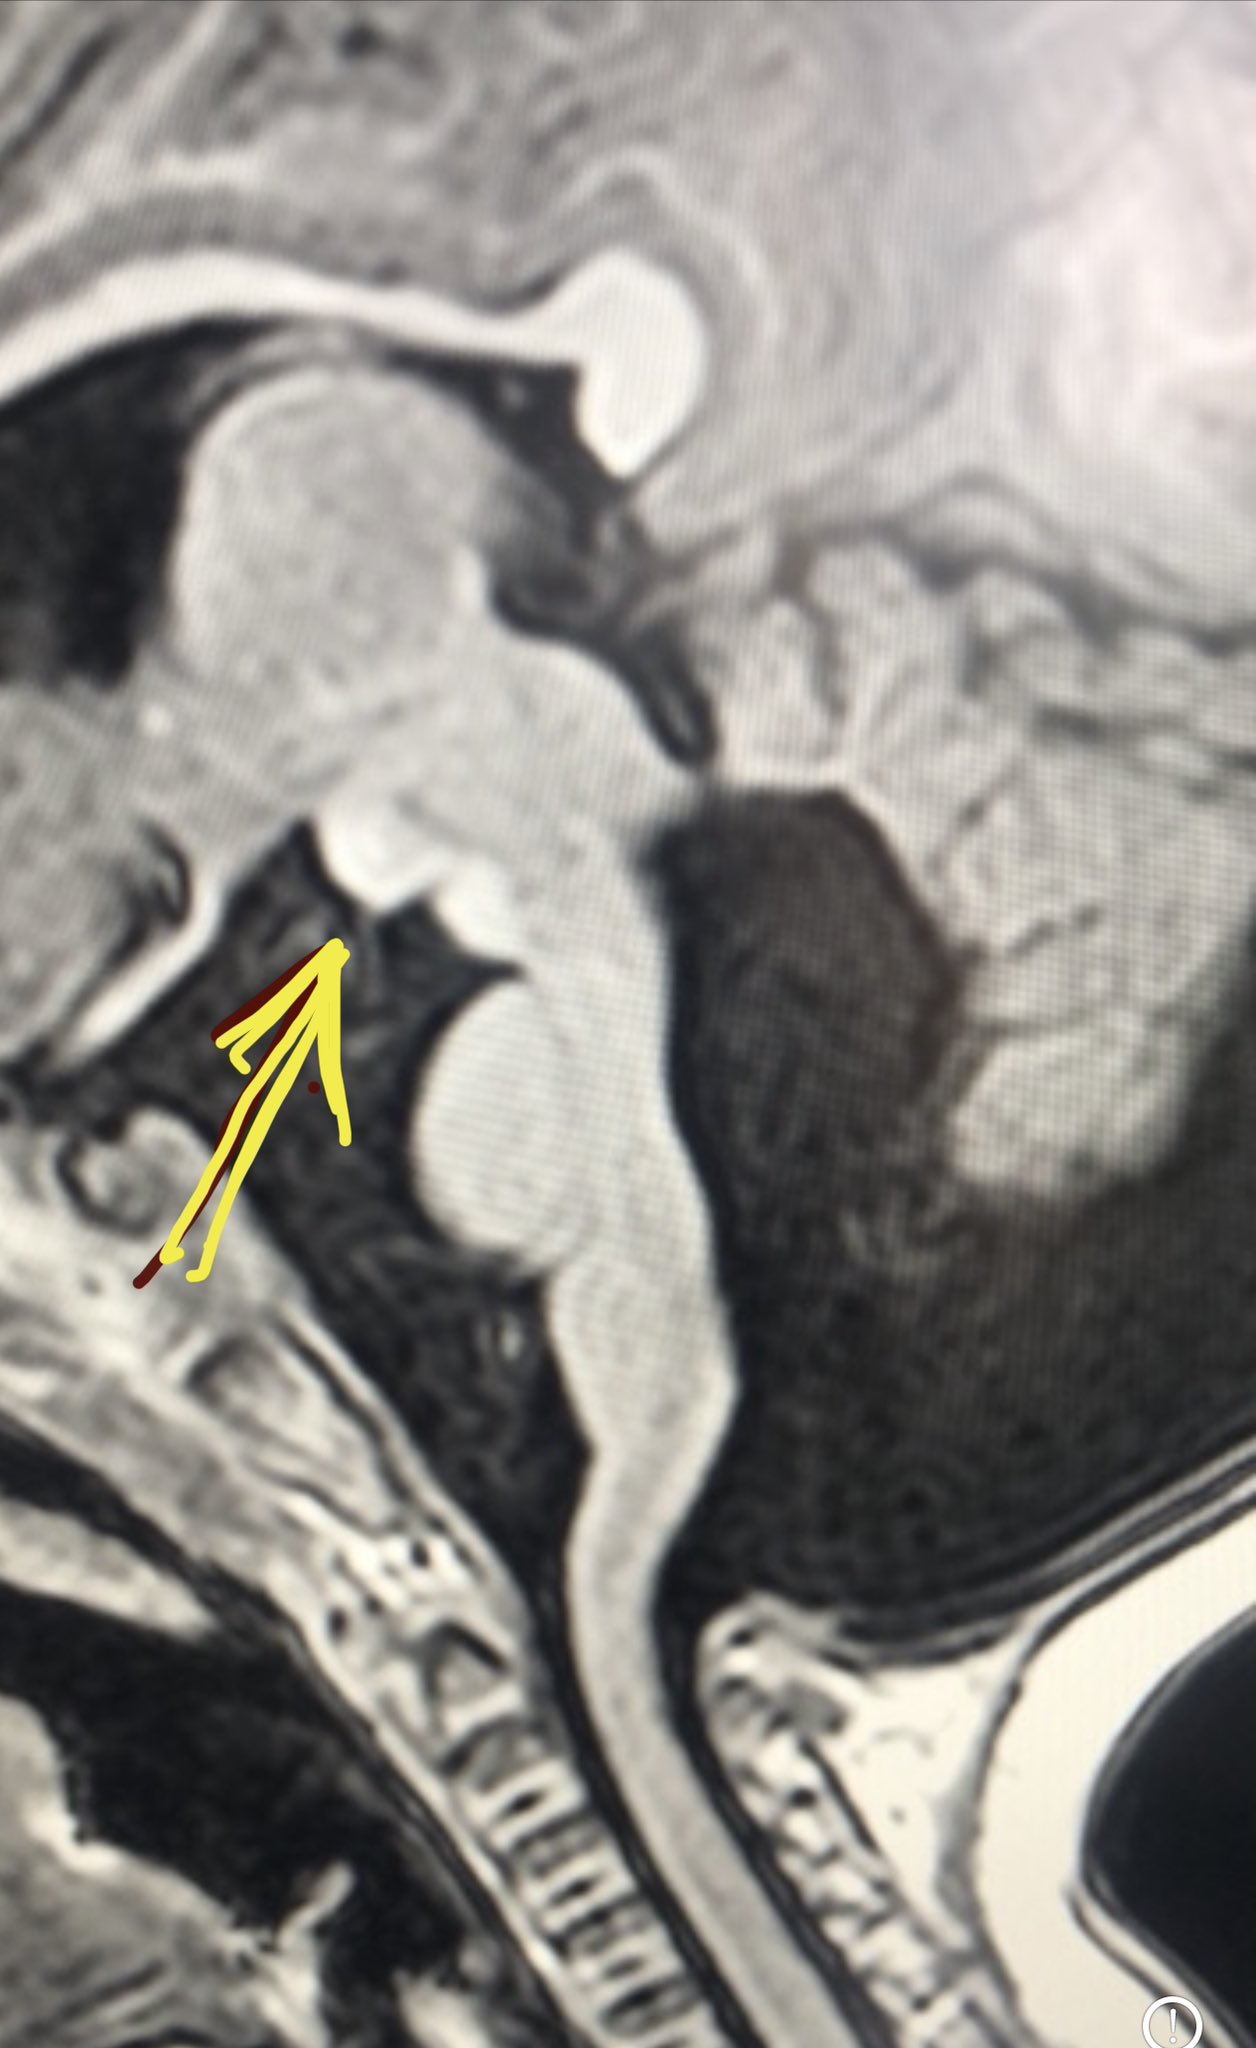

Rmn Cerebral Bucuresti Neuroaxis

Rmn Cerebral Bucuresti Neuroaxis Caps Syndrome Radiology It is defined by an accelerated form of aps, characterized by thromboses, essentially in the small. Caps is a rare condition observed in about 1% of all patients with aps. Caps is a severe manifestation of antiphospholipid syndrome that involves accelerated and widespread thrombosis, which. Caps Syndrome Radiology.